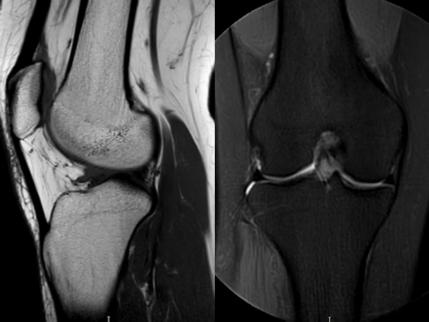

1. “咯吱響”+“卡頓感”——半月板的“碎玻璃警報(bào)”

場景:下蹲時(shí)膝蓋“咯噔”彈響,起身像被“卡住”

MRI偵查:精準(zhǔn)捕捉半月板撕裂或變性(半月板內(nèi)高信號),避免拖成“關(guān)節(jié)交鎖”

(半月板撕裂)